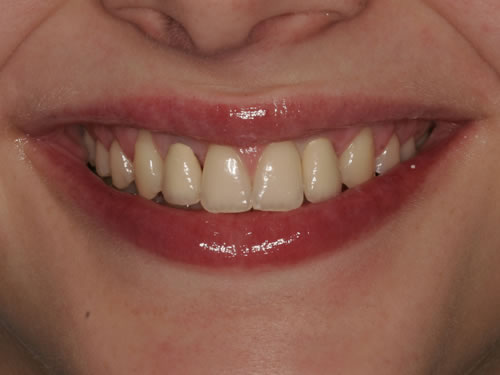

Eine besondere Herausforderung ist die Oberkieferfrontzahnregion. Der Wunsch nach einem perfekten Resultat ist geradezu selbstverständlich. Jeder möchte große, weiße Zähne und ein gesundes, reizloses Zahnfleisch besitzen (Abb. 3.30).

Abb. 3.30: Perfektes Resultat einer Versorgung.